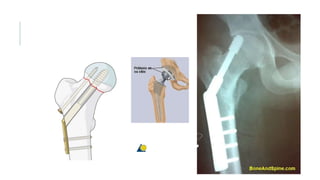

TRATAMIENTO.

Debe ser en menos de 48 hrs. Para evitar complicaciones.

Objetivo: devolver funcionalidad, disminuir morbimortalidad, aliviar el

dolor y levantar al paciente lo antes posible.

Tx qx: Cuello femoral: DHS, tornillos canulados (posible en px

jóvenes, con fractura de menos de 48 hrs de evolución y garden I y II?

Protesis.

Intertrocanterica: DHS